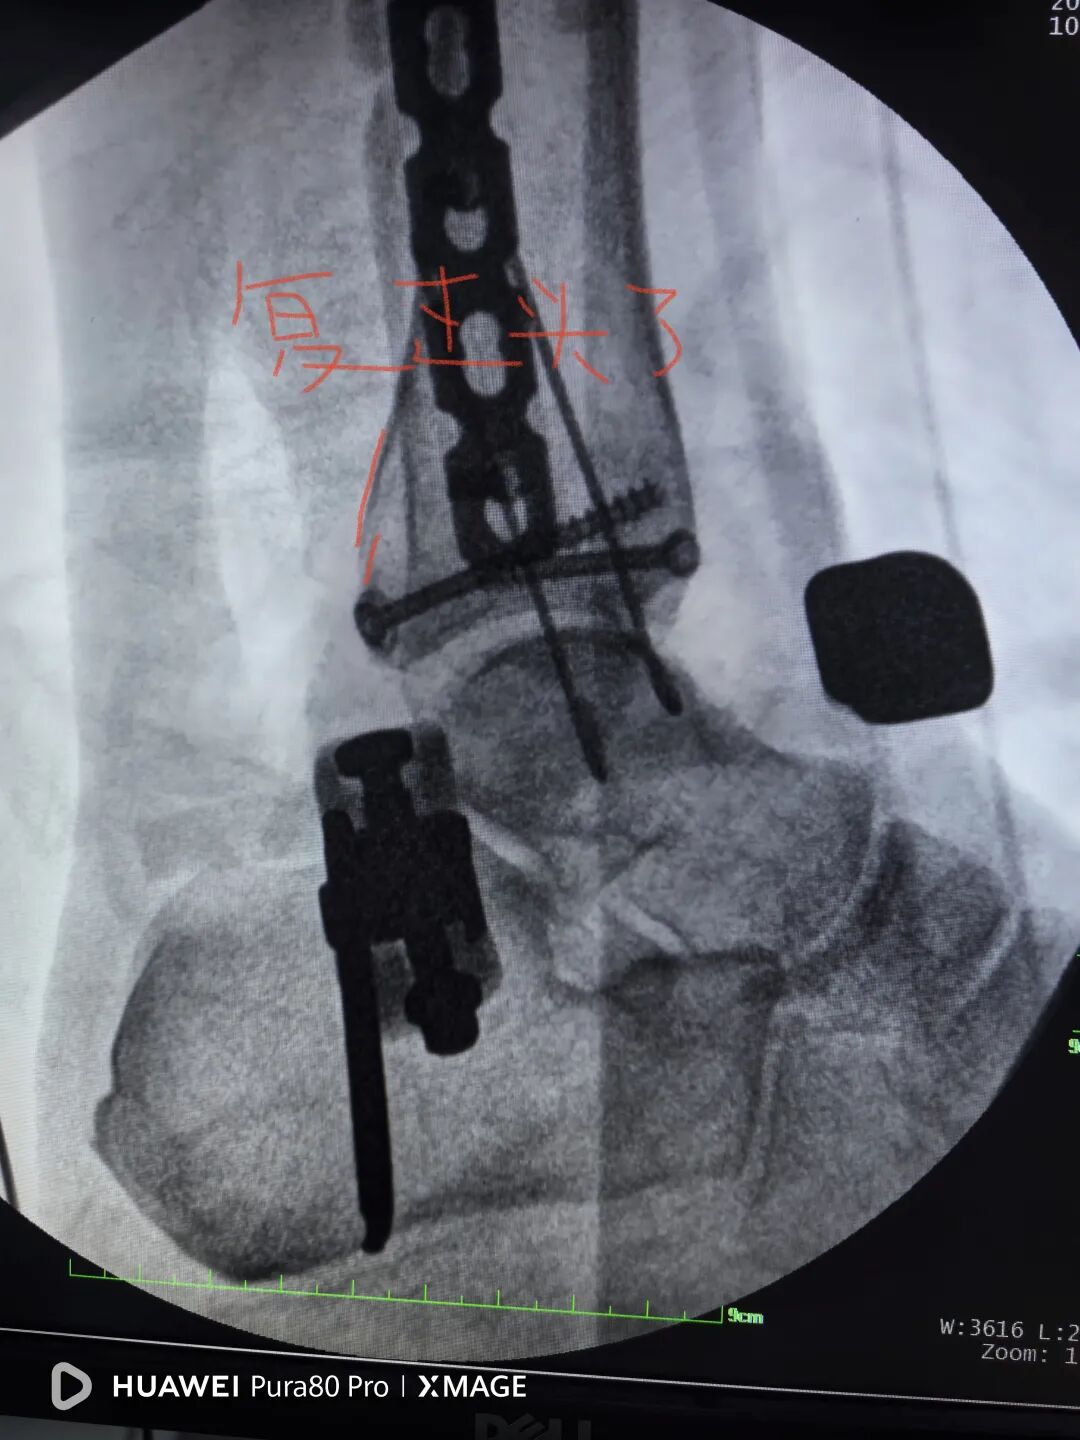

行二次确定性手术

换钉子,调整下方向

解剖复位

最后做下胫腓

两个位置螺钉固定

下胫腓关节复位

内踝间隙恢复